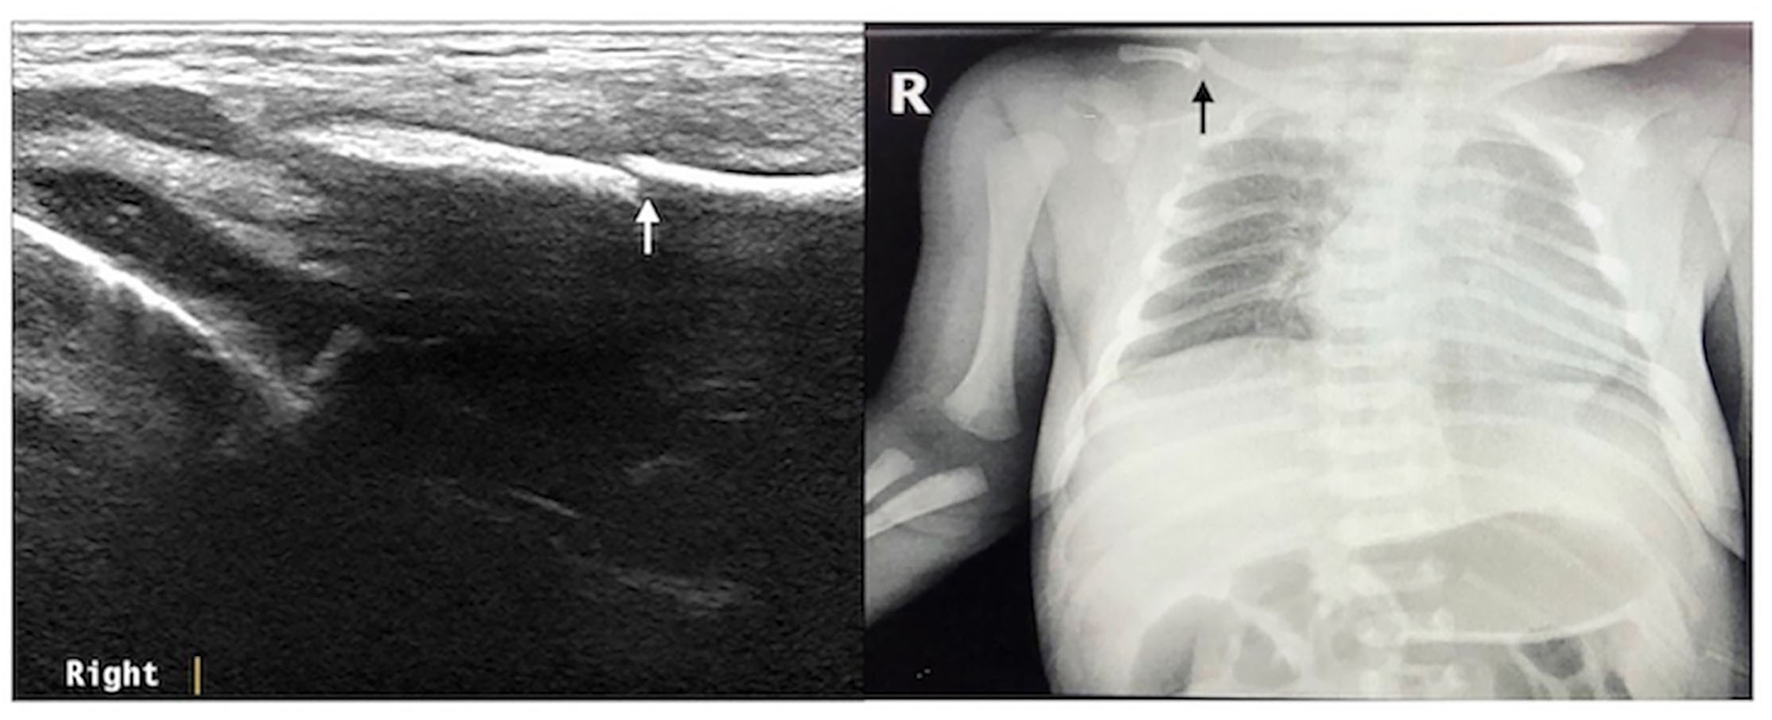

Figure 2

Right clavicle fracture. The infant was G2P1 with a gestational age of 39+1 weeks, vaginal delivery, and birth weight of 4,140 g. The patient was admitted to the hospital 3 h after birth due to intrauterine pneumonia. Physical examination showed that the bilateral clavicles were asymmetrical and that the left side was smooth, while the right side had obvious bone rubbing. Ultrasound revealed interrupted continuity of the cortical bone of the right clavicle and broken end formation and dislocation. The fracture of the clavicle was confirmed by chest X-ray examination.